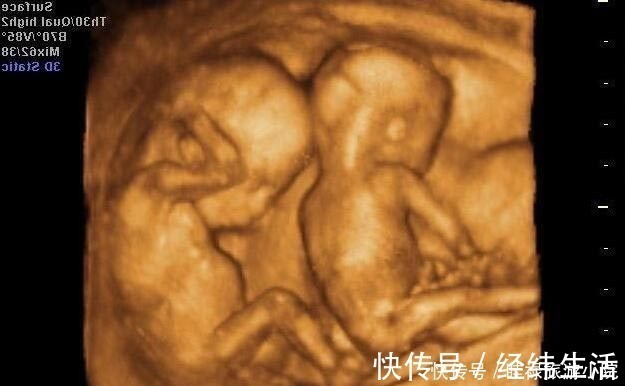

透明膜|孕期产检不想生个“傻孩子”,这三项产检必须按时做,不能忽视( 二 )

以上就是三个在孕期关于“胎儿智力”的检查,不少孕妈觉得自己都挺好的,会忽略产检,但其实每次产检都有意义也很重要,尤其这样的排挤检查,一定都要查查,别不当回事。关注「京妈说」,学习更多专业实用的母婴育儿知识,如果你喜欢这篇文章,要给京妈点赞并分享给更多的人。